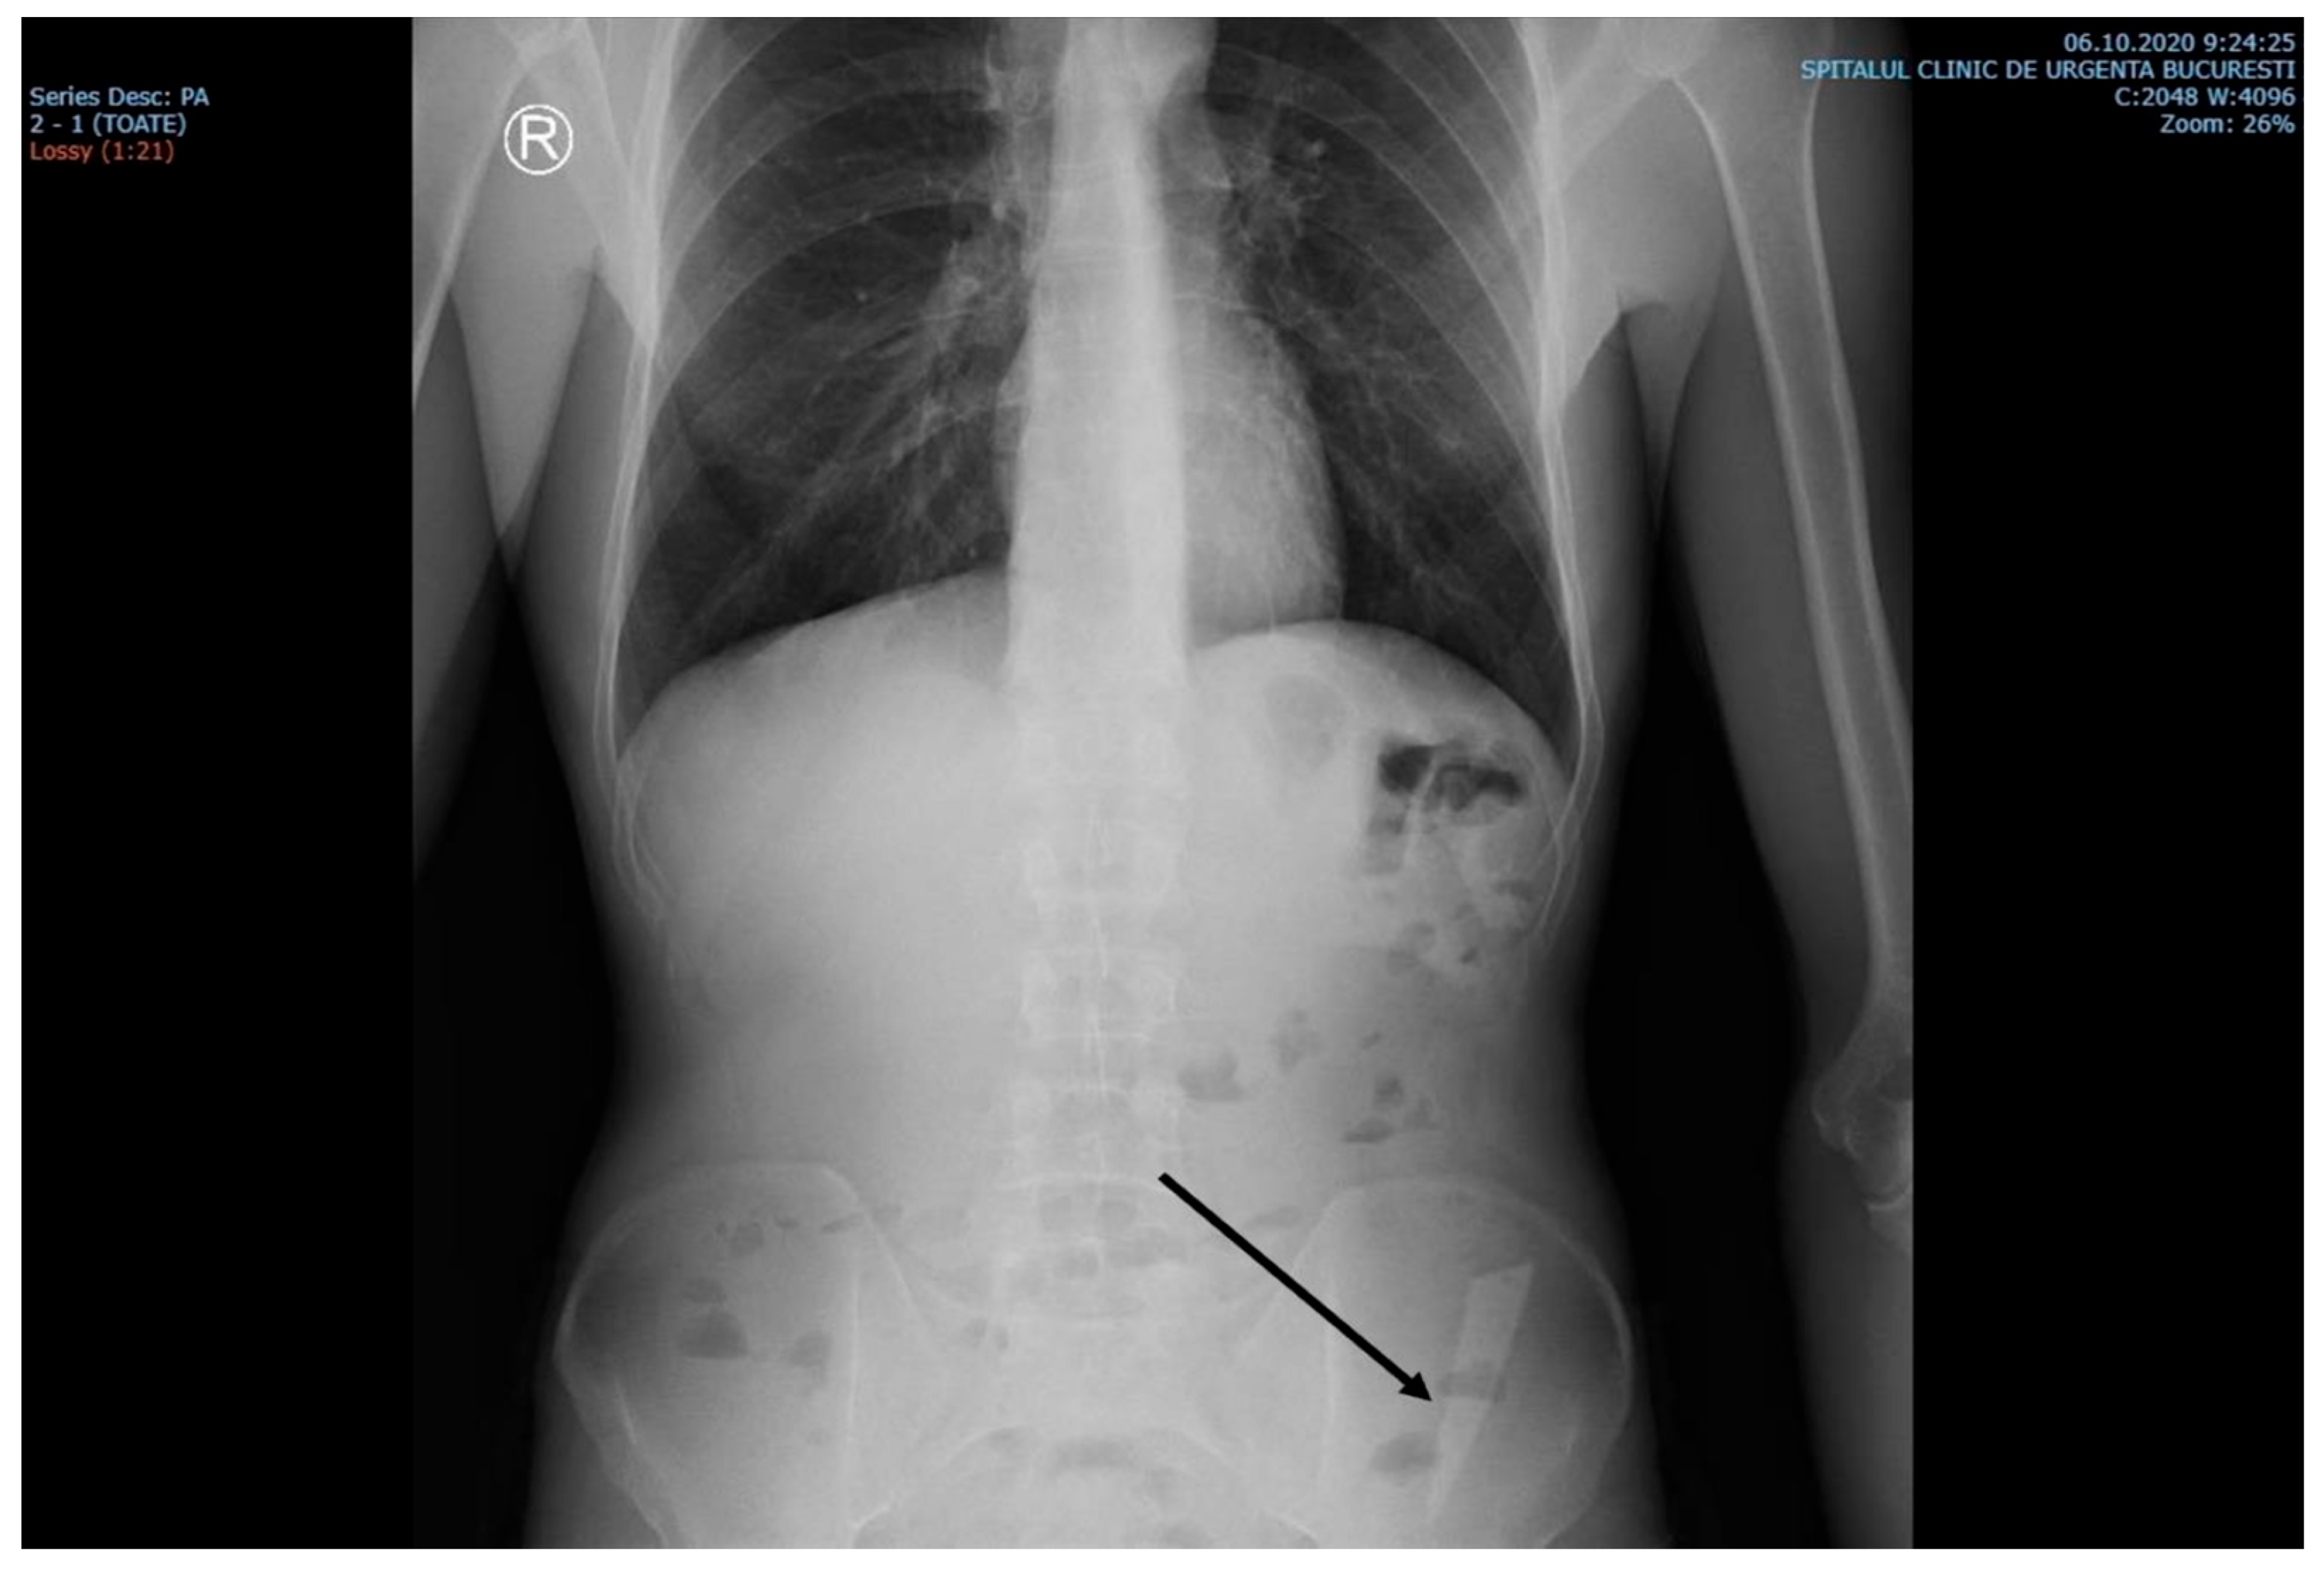

The laboratory examinations of the patient showed leukocytes = 9830/μL, hemoglobin = 12.8 g/dL, platelets = 379,000/μL, ALT = 69 U/L, AST = 48 U/L, PT = 13.6 s, and the rest within normal limits. A chest X-ray at admission showed no acute pleuro-pulmonary lesions. An abdominal X-ray at admission showed discrete aerocolia without radiologically noticeable pneumoperitoneum, hydroaeric levels, and a radiopaque structure in the left flank, denoting a foreign body (Figure 1).

Figure 1. X-ray examination showed an elongated blade (arrow) in the iliac fossa, possibly in the sigmoid colon.